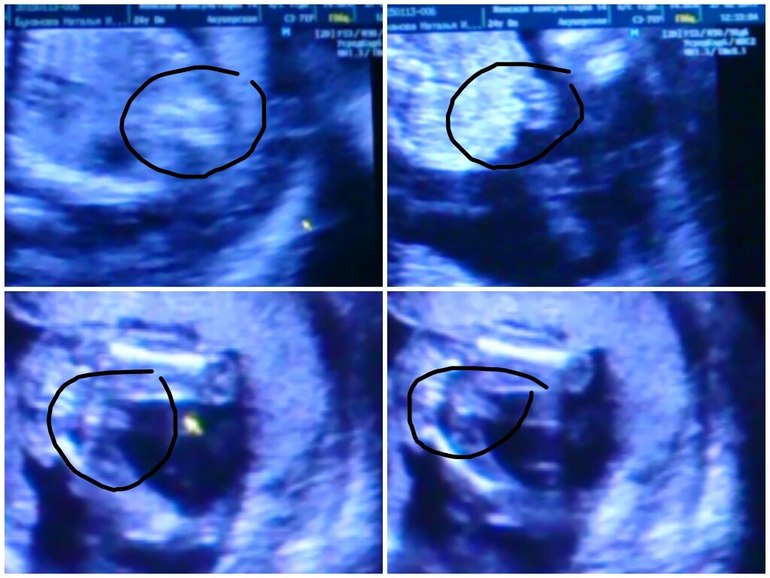

Особенности УЗИ при определении пола ребенка

Раздел: Идеи и советы